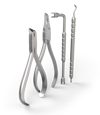

Корректор класса II Вильямса (исполнение 3) - Набор 320-0100

Описание товара

Характеристики